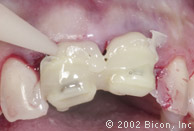

Установка готовых конструкций

Плотный контакт «металл – металл» абатмента и стенок имплантанта обеспечивает надежную фиксацию и бактериальную непроницаемость соединения

Окончательный результат. Превосходная эстетика!